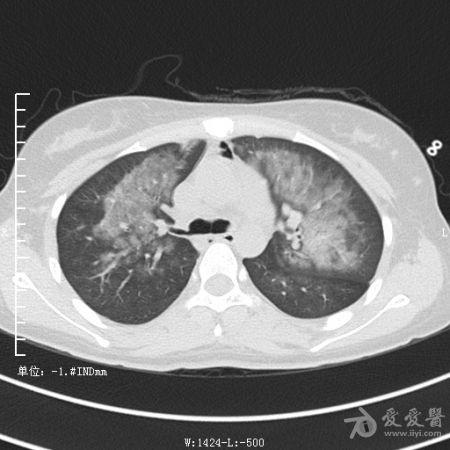

典型支气管扩张及肺水肿CT片

典型支气管扩张肺水肿